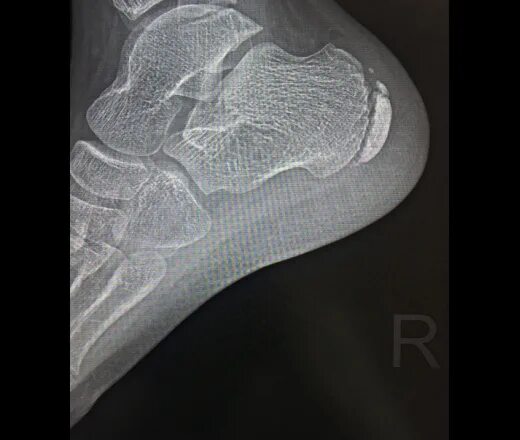

Болезнь шинца у детей код по мкб